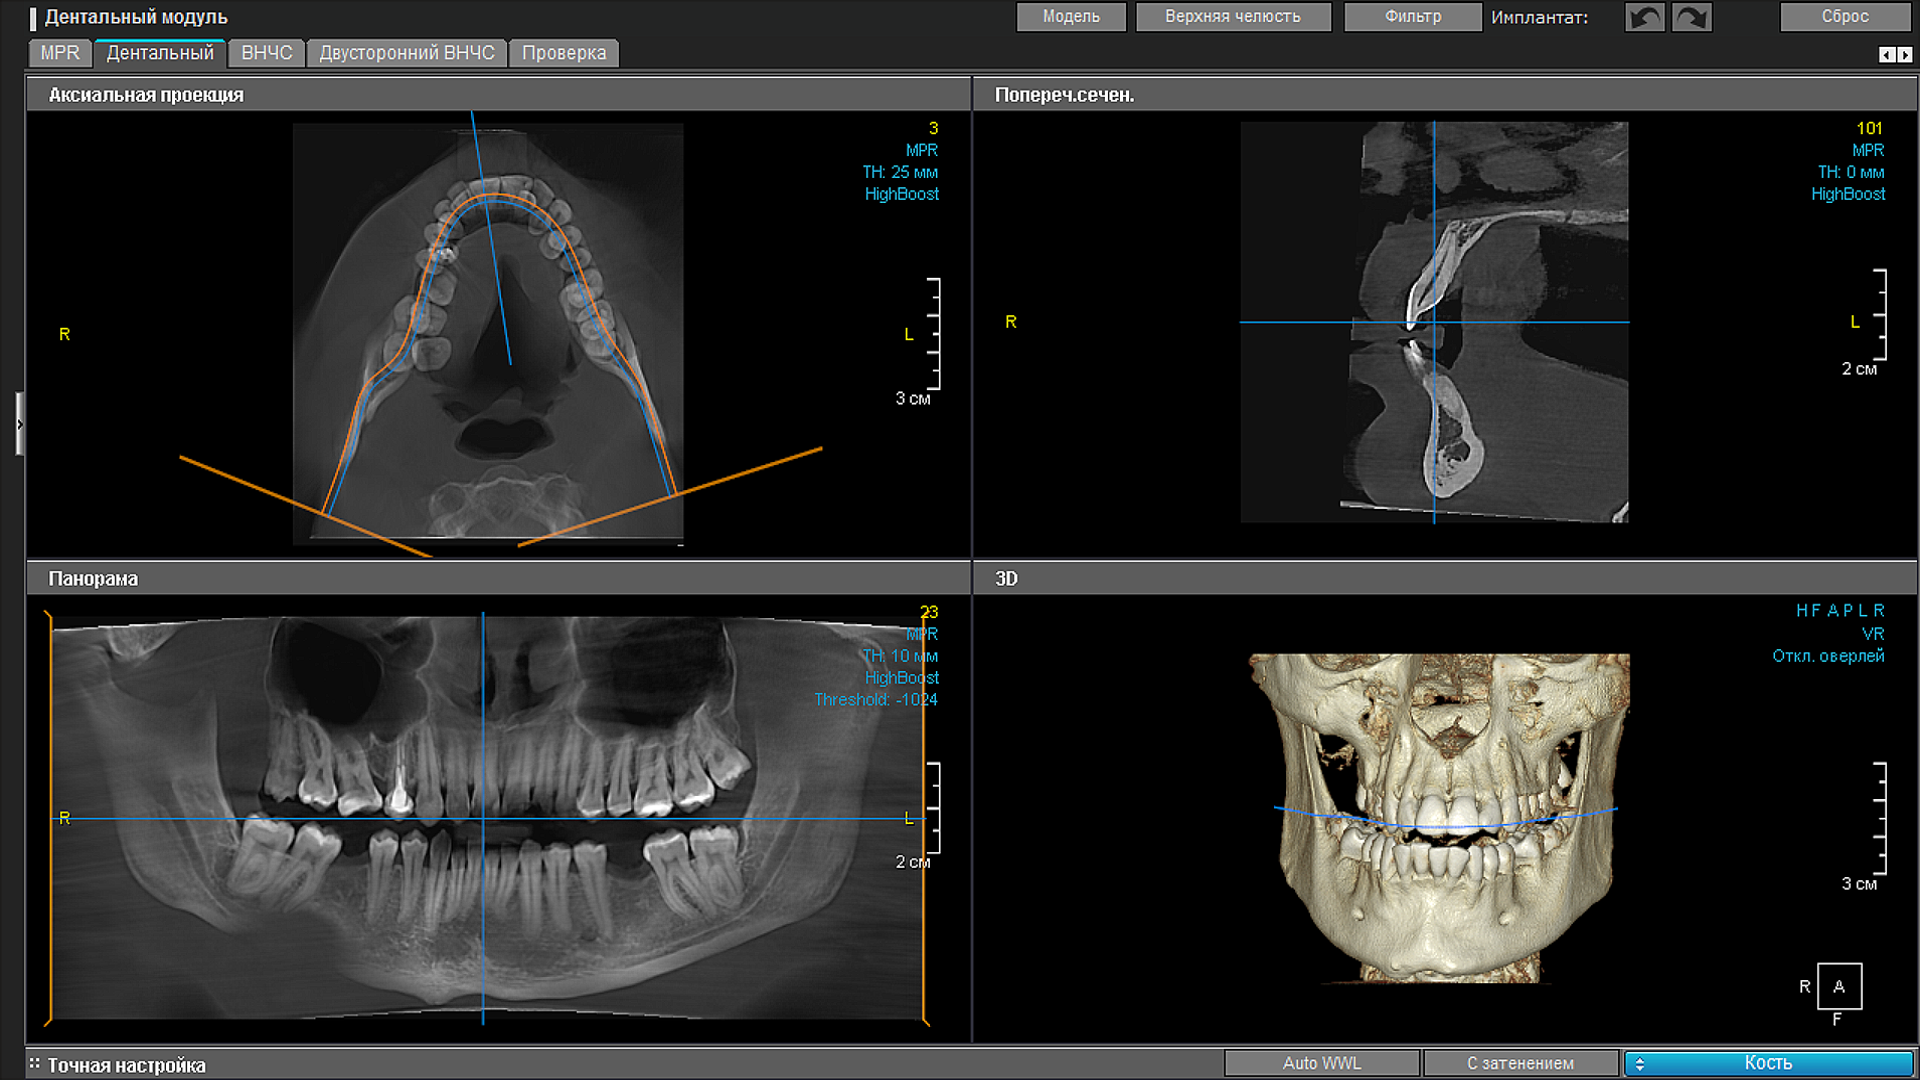

OnDemand дентальный модуль

OnDemand3D dental module

Panoramic tomography of dentitions